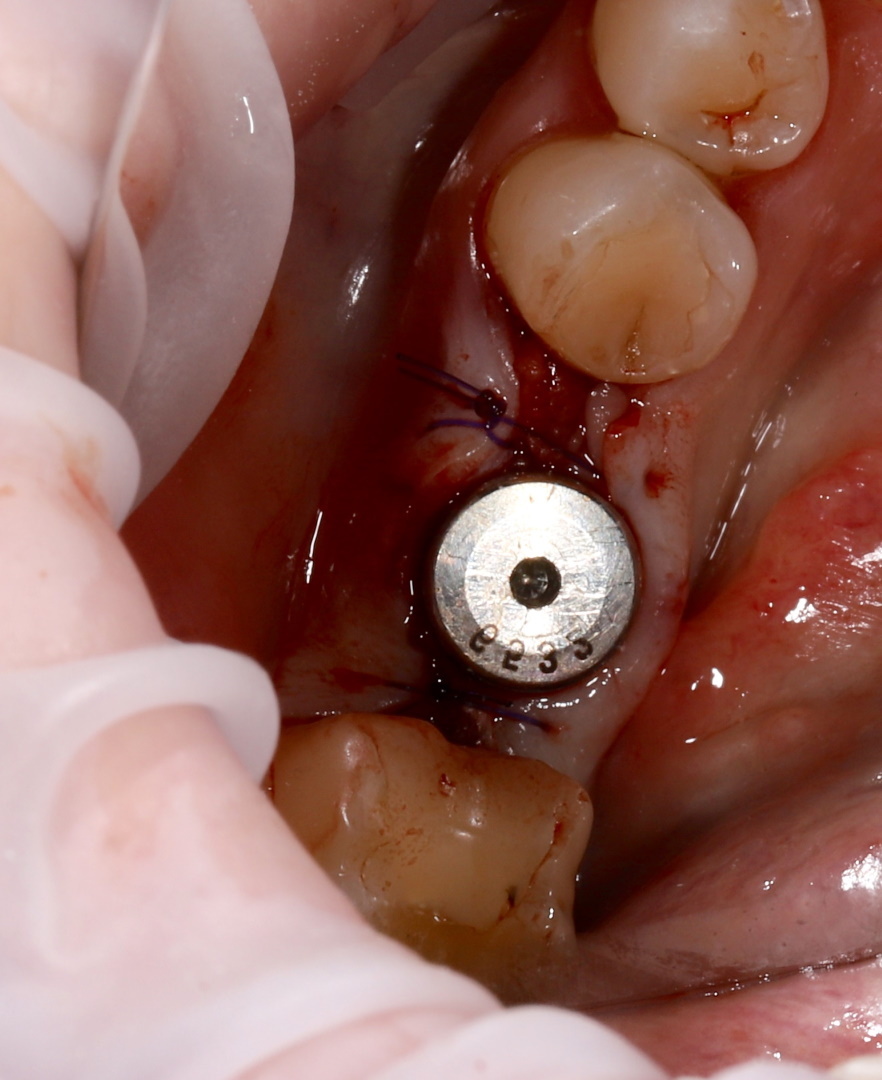

Ранее удаленный зуб 36 - незначительная атрофия по костным тканям и довольно выраженная атрофия по мягким тканям.

Имплант Straumann BLT 4.1*8mm SLActive - установлен в субкрестальное положение, произведено профилирование кортикальной кости системой Straumann Bone Profiler с целью создания более выгодного профиля прорезывания и исключения костной резорбции в области шейки импланта.

Чтобы компенсировать недостаточный объем мягких тканей проведена - мягкотканая пластика деэпителизированным соединительнотканным трансплантантом с неба.

Установлен заживляющий абатмент диаметром 6.5 мм.

Обратите внимание на объем и качество мягких тканей в области будущей финальной реставрации!